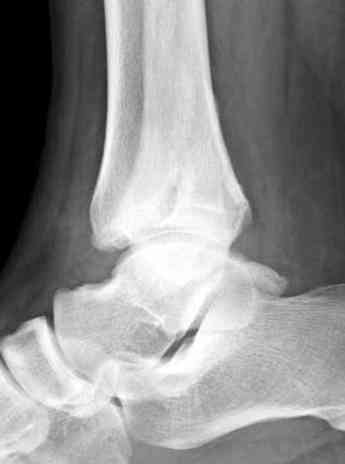

Здесь представлено решение похожей проблемы. Больной в течение года

лечился консервативными мерами, и боли в голеностопе были основным

показанием к операции.

Проведена обычная стандартная процедура по исправлению

неудовлетворительного состояния голеностопного сустава, где кроме

удлинения малоберцовой с применением compression tension device за

проксимальный конец пластины, проведено замещение трикортикальным

графтом из крыла, освобождение синдесмоза и медиальной щели от

фибротических масс с фиксацией.